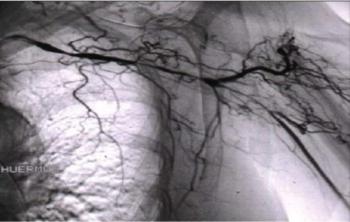

The large vessel vasculitis is more common among older adults and extremely dangerous if missed. Get answers to 3 questions you should ask.